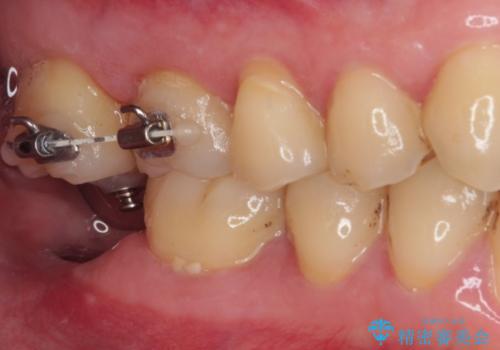

- 左下欠損部のインプラント治療を希望して来院された患者様です。

左下の欠損部を長期間欠損を放置していたことで、咬み合う上の奥歯が動いてしまっていたので、まずは上顎奥歯の部分矯正を行うこととしました。

理想的な咬み合わせに改善した上で、インプラント補綴治療を行うこととしました。